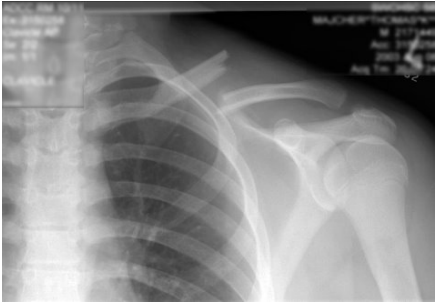

52 45 歲女性,踩在椅凳上擦窗戶時不慎向後跌倒,肩部著地損傷,肩部疼痛、腫脹,呈「方肩」畸形, 彈性固定於肩外展 20~30 度位置,肩關節照 X 光片如圖示,請問診斷為何?

(A)肩關節後脫位 (B)盂下脫位 (C)喙突下脫位 (D)鎖骨下脫位